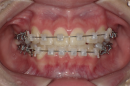

●7か月後

前歯部のトルクコントロール、上下顎の正中の一致、犬歯関係、大臼歯関係が良好になり、咬合関係が改善。(写真c)

画像3: https://www.atpress.ne.jp/releases/360206/LL_img_360206_3.png

c:7か月後